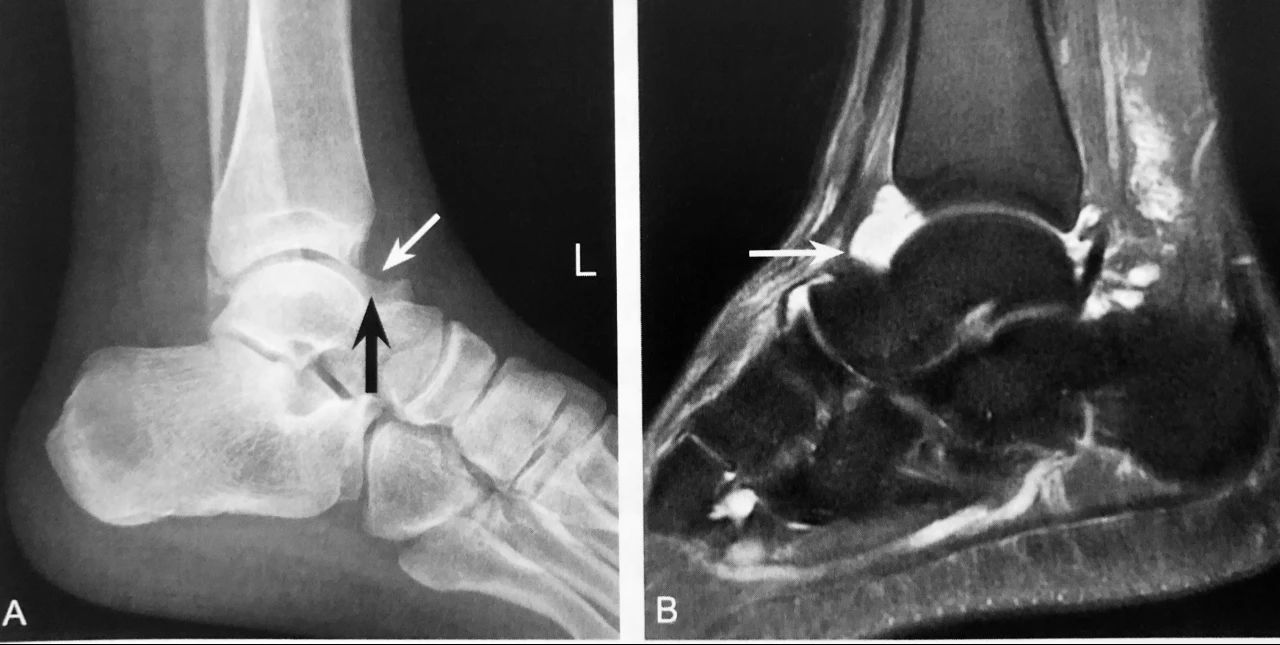

踝 关 节 泪 滴 征

A~E.为同一踝关节外伤患者。A.Ⅹ 线侧位片见“泪滴征”(粗箭头),低密度前脂肪层受压移位变窄(细箭头),提示踝关节积液;B、D分别为踝关节积液MRI、CT表现(长箭头);C、E分别为距骨左份关节面下隐匿性骨折 MRI、CT 表现,MRI 示稍长 T2、长 T1信号,邻近距骨骨皮质连续性可疑中断(三角),CT 进一步明确距骨左份关节面下隐匿性骨折存在(三角)

判读要点:

1、踝关节泪滴征在踝关节 ⅹ 线侧位片上观察;

2、表现为前关节囊内形似“泪滴样”的软组织密度影,范围可从胫距关节纵行延伸至距骨颈骨质前缘;

3、踝关节泪滴征提示各种原因所致的踝关节积液,踝关节外伤后伴随的踝关节积液是提示隐匿性骨折的间接征象;

4、X 线片显示外伤后踝关节积液表现为前、后关节囊肿胀≥15mm,提示隐匿性骨折的敏感性和特异性分别为83%和86%。